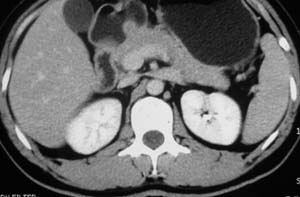

以下是引用子期在2010-3-19 20:47:00的发言:[br]血管畸形的ct增强应该有明显强化,本例并不相符合。本例双肾局部的略低密度影,累及肾盂,局部皮质明显变薄、内陷,增强扫描有轻度的强化,应考虑为炎性病变,患者为年轻男性,累及双肾的感染以结核较常见,可以没有明显的临床症状,尿中有时候也并不能查出什么;肾脓肿常有明显感染中毒症状,本例不符,另外一般的肾盂肾炎或肾小球肾炎通过小便就可确诊,其它还不能排除的是黄色肉芽肿性肾盂肾炎,然而单凭ct一般也很难鉴别。